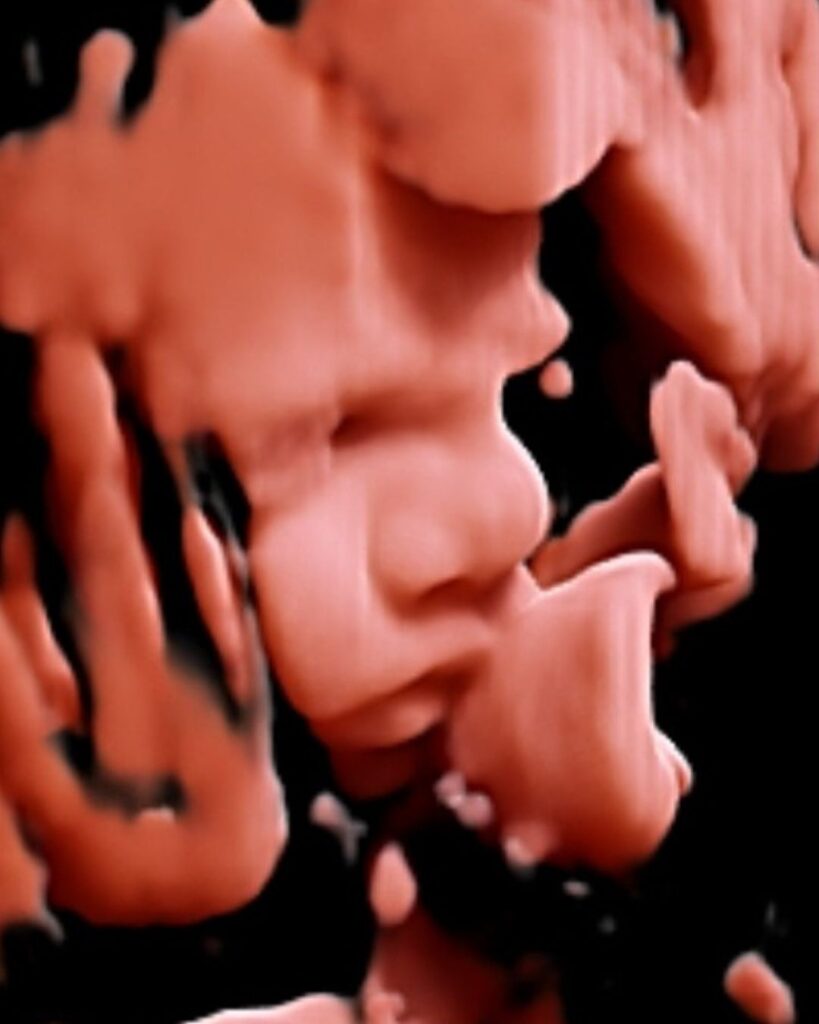

3D echo

20-27 weken zwangerschap

De baby is nu vaak goed geschikt voor een 3D pretecho.

Stilstaand driedimensionaal beeld

Zicht op gezichtje en lichaamsvormen

Meer diepte en detail dan 2D

4D echo

24-32 weken zwangerschap

Een 4D echo laat bewegende 3D-beelden zien (live beeld).

Bewegende gezichtsuitdrukkingen

Gapen, lachen of duimen

Een realistisch beeld van je baby